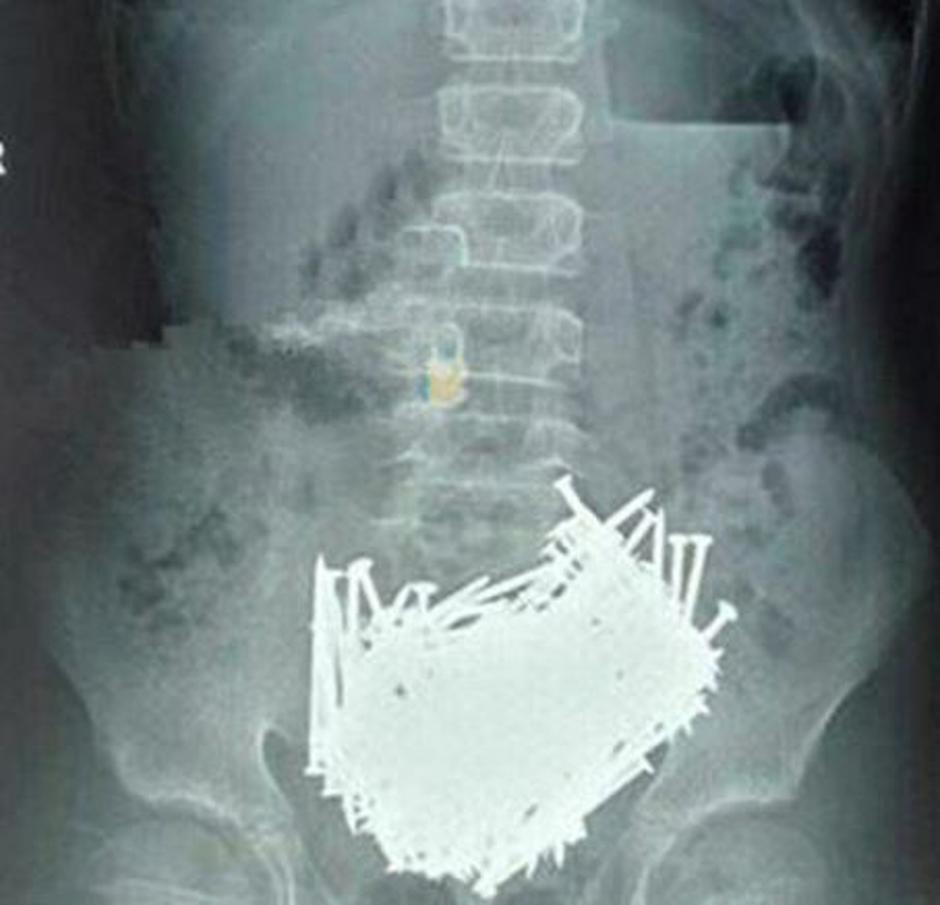

V trebuhu dva kilograma železa

Tudi osebje bolnišnice Sangei Gandhi v Indiji je doživelo šok. 35-letni Maksud Khan je imel v želodcu 263 kovancev, na ducate britvic, 15 centimetrov velik kos zarjavele železne skodelice, štiri velike igle, nekaj kosov stekla, v njegovem trebuhu pa so našteli tudi sto žebljev. V trebuhu moškega se je nabralo za dva kilograma železa.

Khanovi sorodniki so povedali, da je nesrečnik trpel zaradi hude depresije: "Kadarkoli je občutil potrebo po zaužitju kovanca, ga je pač pojedel in to tako, da ga je poplaknil z vodo," je dejal eden od družinskih članov.